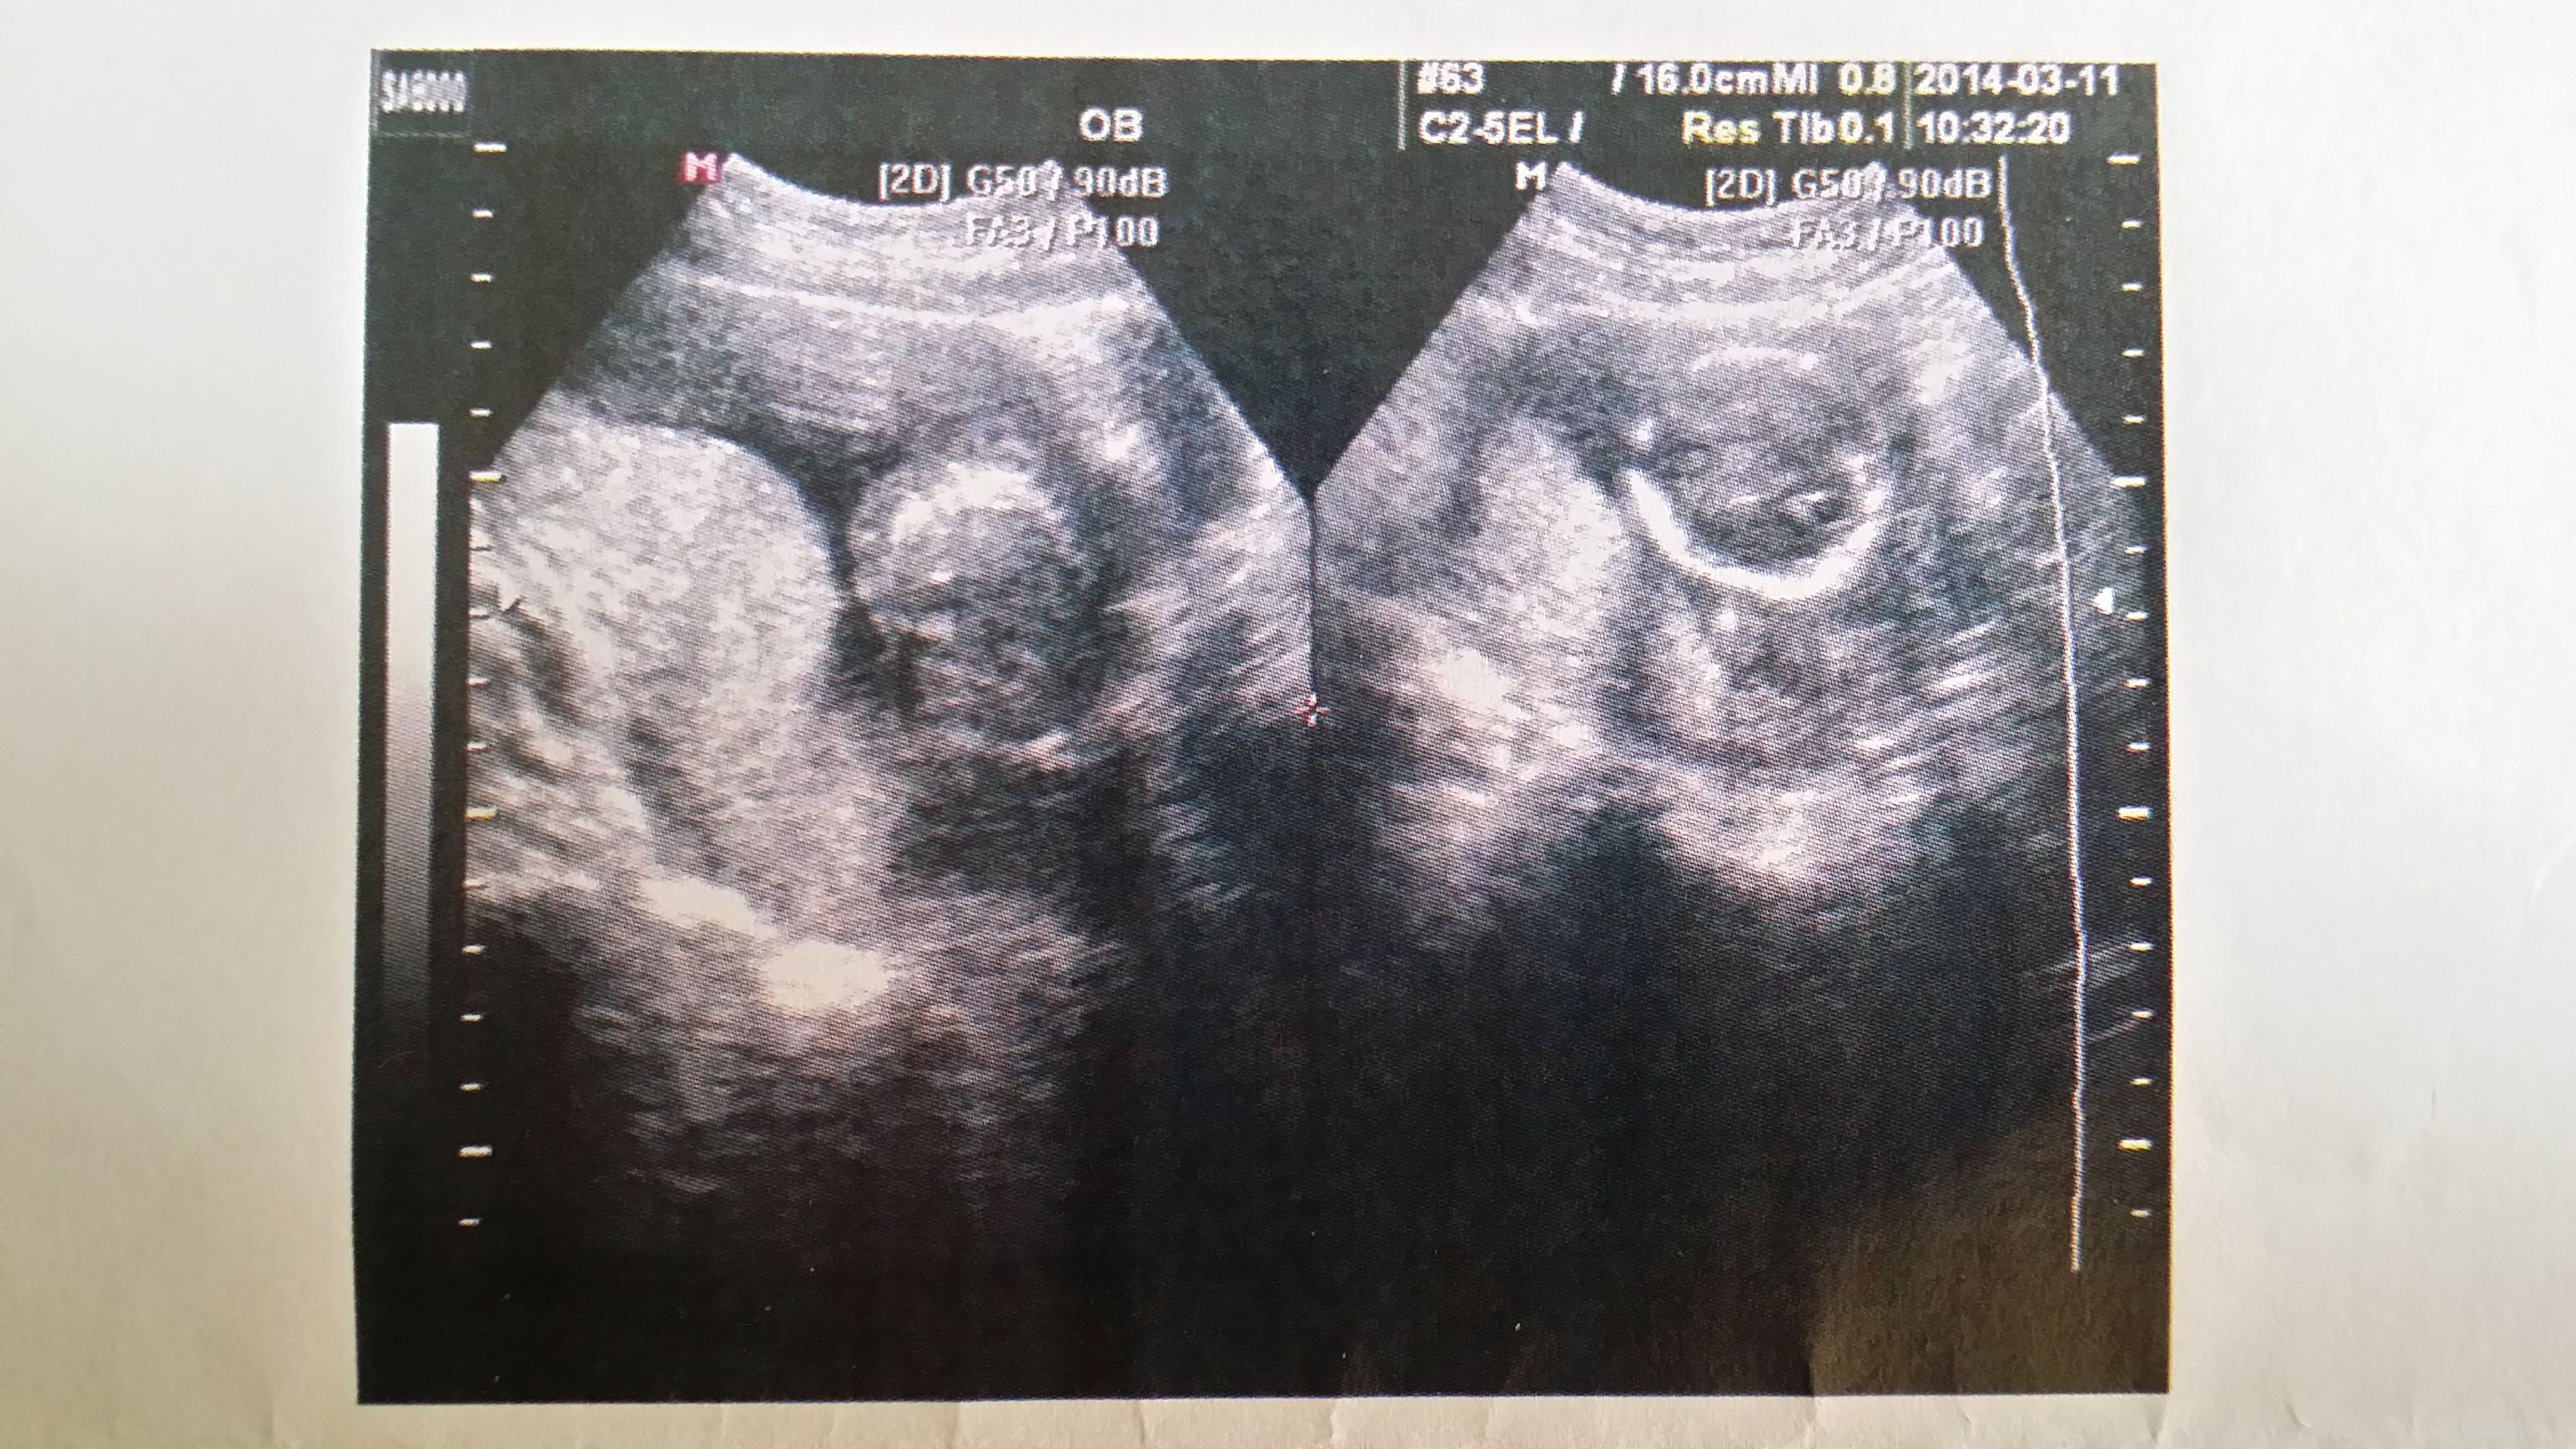

哪位大神能帮我看看这份B超单 宝宝性别 在线等 万分感谢 点击展开 匿名用户 2014-04-26 13:37 满意回答 没有显示生殖器,看不出来,祝你心想事成。 碧坚秉_xr4J 2014-04-26 21:49 宝宝知道提示您:回答为网友贡献,仅供参考。 为您推荐: 其他回答 男性 从心率可以看出来 女性在150以上 匿名用户 2014-04-27 11:11 还没有性别,再等等 匿名用户 2014-04-27 00:02 相关问题 有懂行的宝妈吗,帮我看看胎儿性别,万分感谢 做B超声波要几个月才能分辨出胎儿的性别?大神们帮帮忙 qq宝宝斗场求大神帮我看看该用什么宝宝,明天就领麒麟和13级送的神宝宝